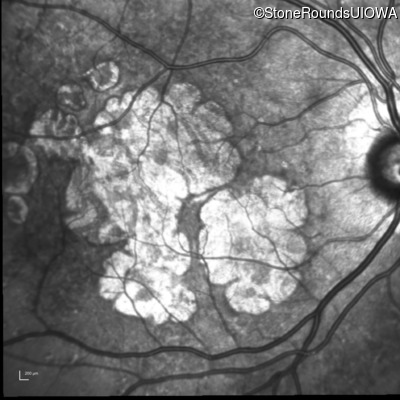

AR Stargardt Disease (IIA)

Age at visit: 59 years

This 59 year old man has noticed some blank spots near the center of his vision over the last 2 years.

Diagnosis & molecular findings

Disease Gene Allele 1 variant(s) Allele 2 variant(s) Inheritance mode

AR Stargardt Disease ABCA4 Leu2027Phe CTC>TTC IVS30+1321 A>G AR